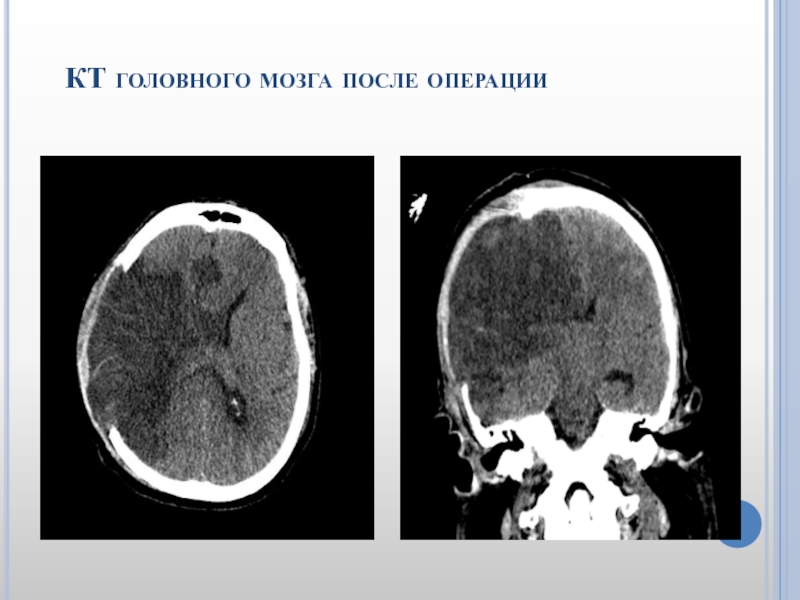

Слайд 32 КТ головного мозга после операции

Слайд 31 Пациентке на 2 сутки выполнена декомпрессивная трепанация

черепа